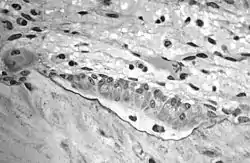

В сформировавшейся кости остеобласты встречаются только в местах разрушения и восстановления костной ткани, тогда как в развивающейся кости они непрерывным слоем покрывают почти всю поверхность формирующейся костной балки. Остеобласты располагаются вокруг первичных костных перекладин, образованных коллагеновыми волокнами. Оказавшись между ними, многие остеобласты замуровываются в межклеточном веществе и становятся остеоцитами. Так возникает костная ткань.